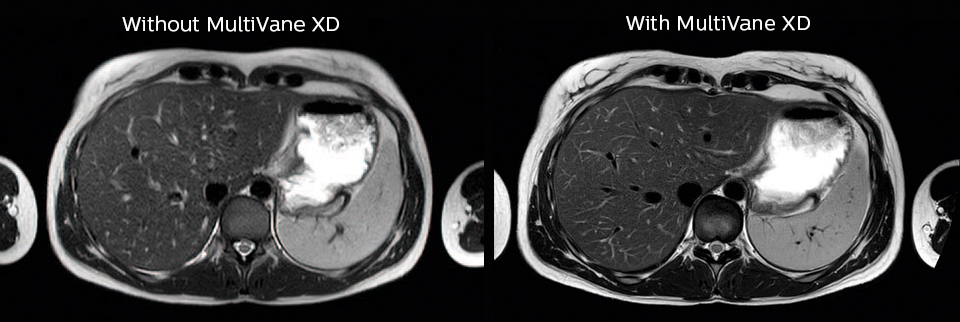

“We also love MultiVane XD for motion reduction in imaging. We find this a huge step forward. We use it in the head, and of course in the upper abdomen, and the images are outstanding most of the time. And it can be combined with dS SENSE parallel imaging for speed.” “We have compared image quality of FLAIR with MultiVane XD versus FLAIR without MultiVane XD. In 15 of the 40 patients studied, we saw motion artifacts on plain FLAIR brain images. The FLAIR images with MultiVane XD were motion-free in 39 of 40 patients and showed slight motion artifacts in only one patient.”